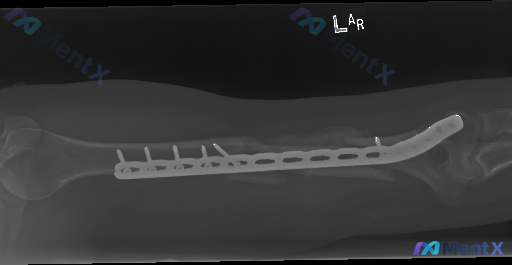

整理到一份左肱骨干骨折内固定术后的影像资料,大家可以先看一下关键表现: 基本背景:左肱骨干骨折术后复查 影像核心表现: - 肱骨外侧可见锁定加压钢板及多枚螺钉固定 - 钢板中段下方骨折区域,皮质不连续,断端存在分离及错位 - 断端周围有模糊、密度增高的骨痂形成迹象,但部分区域断端间隙仍可见,骨质连接...